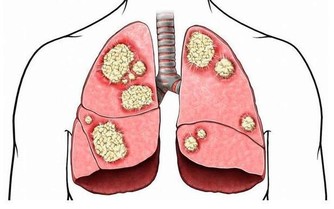

肺火旺盛咳嗽:反覆咳嗽、咳黃痰,伴有口乾、咽痛、便秘、尿赤、身熱或伴有喘息等症狀。